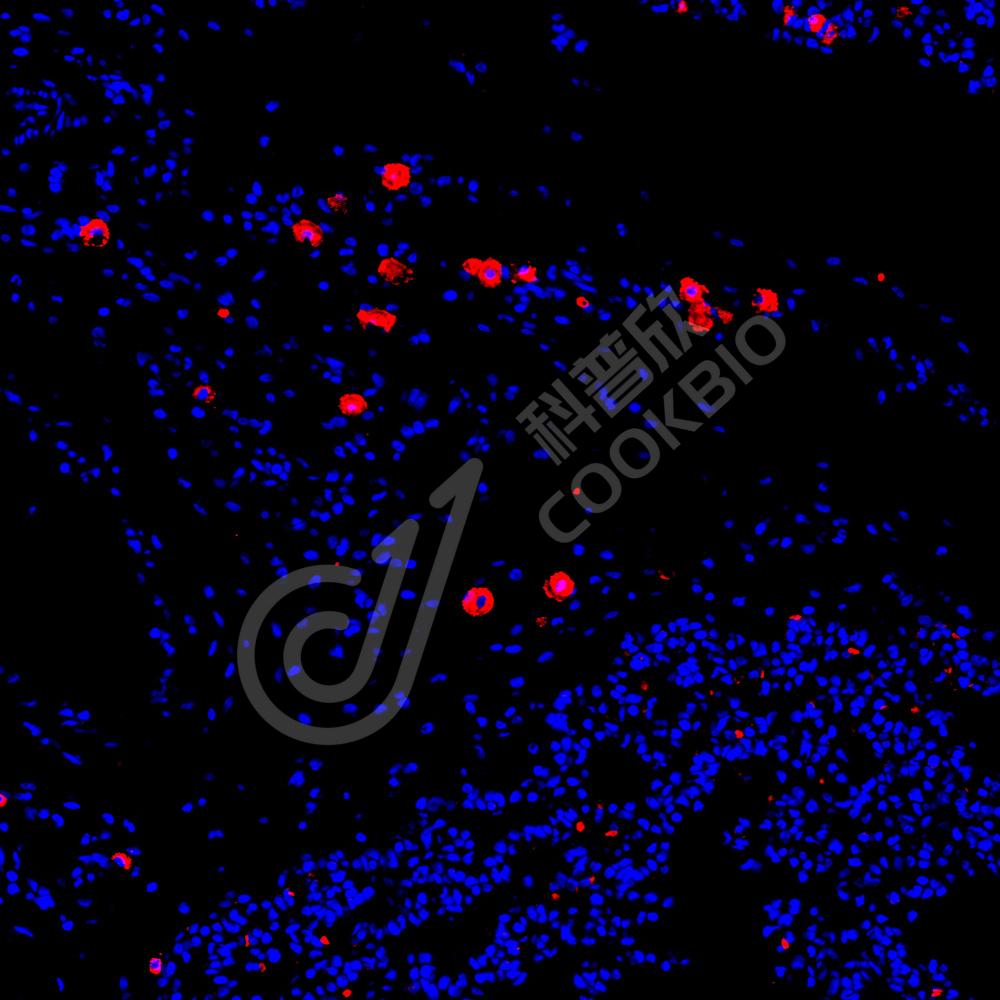

IF检测IL-9蛋白(货号 K135052)(红色).

样品: 小鼠脾, 4%多聚甲醛 (货号KSG1101) 固定12-24小时.

抗原修复: Tris-EDTA抗原修复液(pH 9.0) (KSG1203), 98℃, 20分钟.

封闭: 3% BSA(货号KSGC305010)的PBS溶液, 室温孵育30分钟.

—抗: 1: 1900稀释, 4℃ 孵育过夜.

二抗: Cy3标记山羊抗兔IgG (H+L) (货号KB63909), 1: 300稀释, 室温孵育1小时.